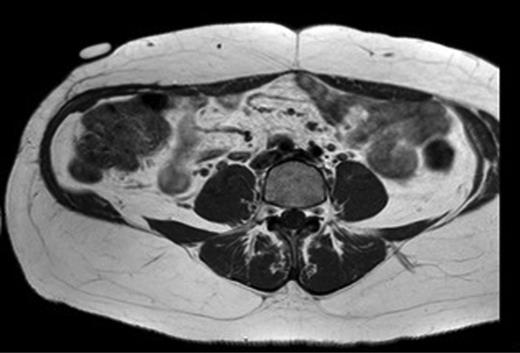

A 31-year-old man presented to his General Practitioner in May 2012 with a 6-week history of a painful mass in the right iliac fossa. There was no regional lymphadenopathy and hip examination was unremarkable. He was a smoker with a BMI of 33 and had undergone a right-sided inguinal hernia synthetic mesh repair in 2010. MRI with contrast confirmed a 6.9 × 6.7 × 4.6 cm mass invading the abdominal wall musculature (Fig. 4). Radiological features were suggestive of sarcoma or aggressive fibromatosis. Histology from an ultrasound-guided biopsy revealed aggressive fibromatosis. The patient opted for a surgical excision of the mass with abdominal wall reconstruction. The tumour was excised with the internal oblique, leaving the peritoneum and external ring cord structures intact. A 13 × 15 cm sheet of porcine intestinal biological mesh was used to repair the abdominal wall defect (Fig. 5). Inferiorly, the mesh was doubled over in the pre-peritoneal space to reconstruct the inguinal ligament, and sutured to the external oblique. The histology confirmed a final diagnosis of aggressive fibromatosis excised with 1 mm margins. At 24 months, there was good wound healing and no hernia, seroma or evidence of recurrence on follow-up MRI.

T1 MRI showing a soft tissue tumour of the anterior abdominal wall involving external oblique and internal oblique and not involving the peritoneum.